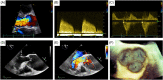

Aortic regurgitation (AR) is a common valvular pathology. Multimodality noninvasive cardiovascular imaging is routinely used to assess the mechanism of AR, degree, and its hemodynamic impact on the cardiovascular system. Collecting this information is crucial in establishing the prognosis and in guiding patient management and follow-up. While echocardiography remains the primary test to assess AR, a comprehensive assessment of this valvulopathy can be obtained by combining the information from different techniques. This state-of-the-art review is intended to provide an update ed overview of the applications, strengths, and limits of transthoracic echocardiography, cardiac magnetic resonance, and cardiac computed tomography in patients with AR.